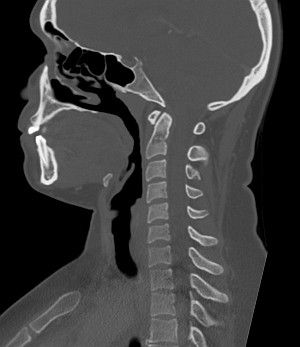

Шейный отдел позвоночника